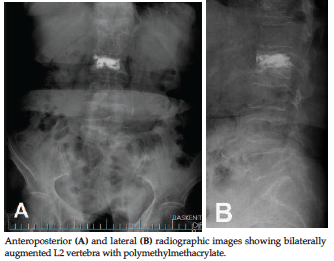

Figure 2. Postoperative Radiologic Images

vertebral body. After removal of balloons, polymethylmethacrylate was injected

(Figure 2).